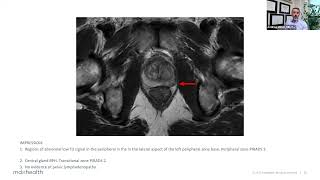

Webinar - ECG for tip location: the new gold standard for all patients ? Lecture: Tips and Tricks for Intraocular Foreign Body Removal

Lecture: Tips and Tricks for Intraocular Foreign Body Removal Generative AI for Healthcare (Part 1): Demystifying Large Language Models

Webinar - ECG for tip location: the new gold standard for all patients ? Lecture: Tips and Tricks for Intraocular Foreign Body Removal

Lecture: Tips and Tricks for Intraocular Foreign Body Removal Generative AI for Healthcare (Part 1): Demystifying Large Language Models